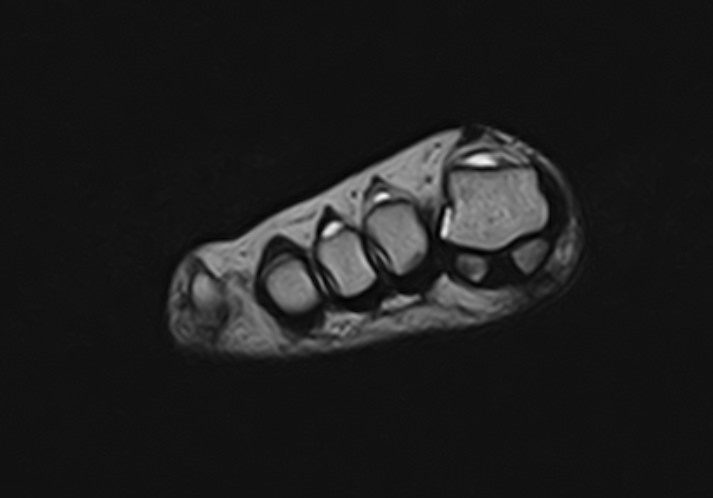

В клинике «Доступная медицина» данное исследование проводится на современном высокопольном магнитно-резонансном томографе экспертного класса TOSHIBA VANTAGE TITAN 1,5 Тесла. Напряженность магнитного поля 1,5 Тесла обеспечивает высокую разрешающую способность аппарата, что позволяет выявлять минимальные изменения в тканях и диагностировать заболевания на начальной стадии.

В большинстве случаев проводится стандартная магнитно-резонансная томография стопы без использования контраста, однако в некоторых случаях требуется контрастное усиление для детализации патологических очагов. Для этого применяется контрастное вещество на основе гадолиния (элемент, относящийся к редкоземельным металлам), которое полностью выводится из организма в течение суток преимущественно почками.